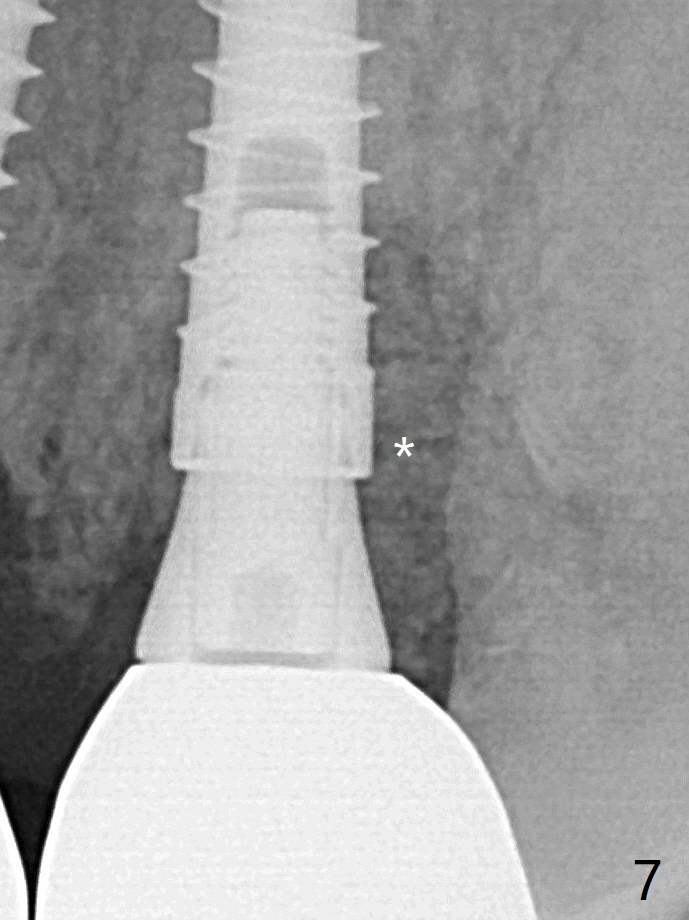

It appears that the socket shield (Fig.16 S) causes infection and loss of bone graft (*).  With periosteal relief and placement of sticky bone (Fig.7 *), PRF and 6-month membrane, the wound is closed with 4-0 PTFE suture (Fig.5).